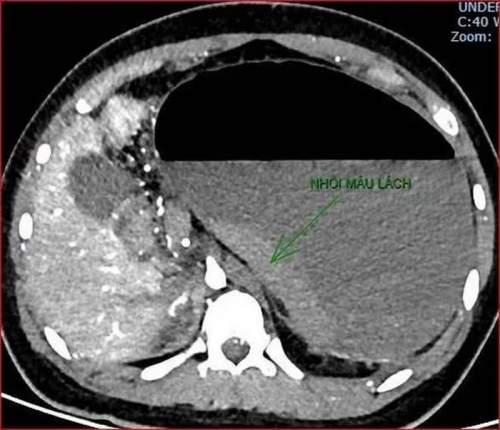

Khoảng 21h40, kết quả chụp CT cho thấy bệnh nhân rơi vào tình trạng cực kỳ nặng và hiếm gặp, bao gồm: Xoắn dạ dày, nhồi máu thận trái, nhồi máu lách, viêm đầu tụy, viêm hỗng tràng, kèm dịch ổ bụng và tràn dịch màng phổi, trên nền bệnh nhân mắc hội chứng Down và tim bẩm sinh.

Kết quả chụp CT cho thấy bệnh nhân rơi vào tình trạng cực kỳ nặng và hiếm gặp. |